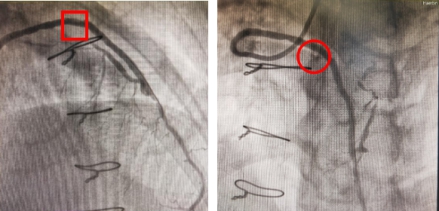

前降支静脉桥血管术前造影影像

前降支静脉桥血管药球治疗术后影像